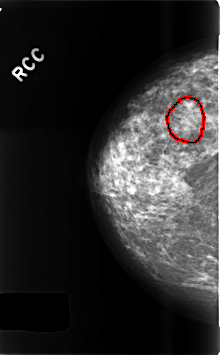

FILE: C_0497_1.RIGHT_CC.OVERLAY

TOTAL_ABNORMALITIES 1

ABNORMALITY 1

LESION_TYPE CALCIFICATION TYPE AMORPHOUS DISTRIBUTION CLUSTERED

ASSESSMENT 4

SUBTLETY 2

PATHOLOGY BENIGN

TOTAL_OUTLINES 1

BOUNDARY